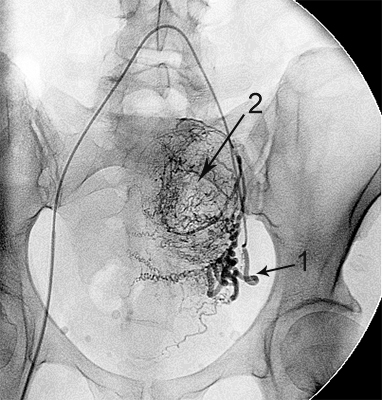

Ангіограми до та після емболізації:

міома матки до емболізації    міома матки після емболізації

Розширена звивиста ліва маткова артерія (1),

вузол лейоміоми матки (2)

Після емболізації частками: маткова артерія

збережена (1), лейоміома не контрастується (2).